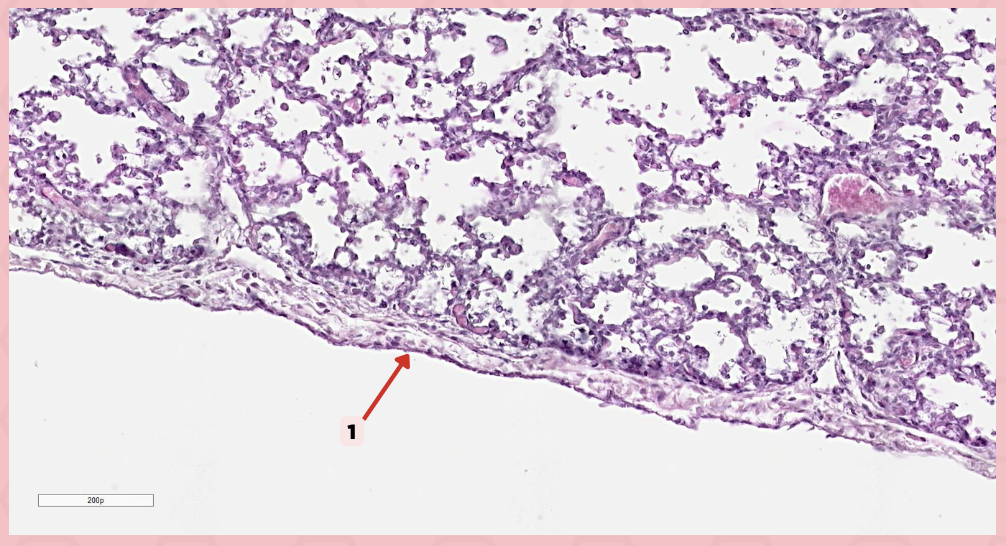

Simple squamous epithelium (Mesothelium)

The surface related to the pleural cavity is in line with what type of epithelium?

Visceral pleura

Identify the structure labeled as 1.

Visceral Pleura

What type of pleura is a thin layer of connective tissues that borders on the outside by mesothelium?

Simple Squamous Epithelium

What epithelium lines the red arrow?

Mesothelium

Identify the structure labeled as 1.